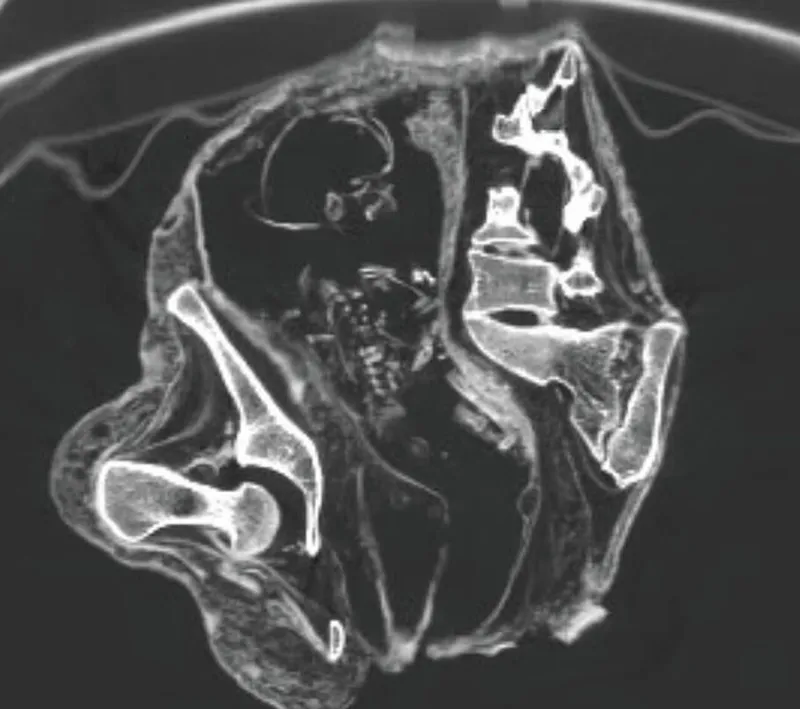

"На снимках компьютерной томографии зафиксирован плод, лежащий на спине головой вниз, в районе живота и грудной клетки, а руки расположены ближе к тазовой области", – говорится в статье.